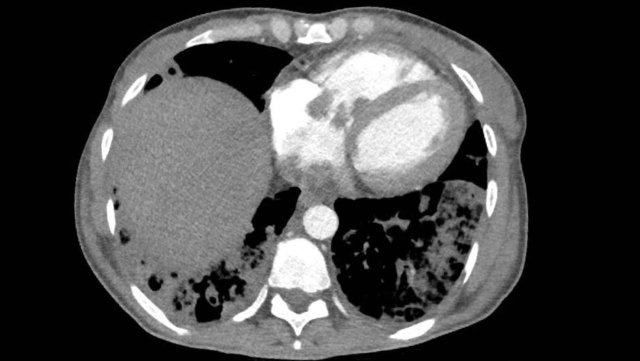

Image

Subendocardial fibro-fatty replacement after a prior infarction in the LAD territory.

In the acute phase of a myocardial infarction a perfusion defect may be seen on contrast-enhanced chest CT as hypodense attenuation in a coronary territory.

This may present in scenarios where the patient's initial presentation is related to trauma – such as a traffic accident or fall from stairs – and the triggering cardiac issue is initially overlooked.

This scenario underscores the importance of a thorough evaluation of cardiovascular abnormalities in the early detection of unsuspected pathology.

Perfusion defect in LAD territory of 45 year old trauma patient, who presented after a fall from the stairs during heavy lifting.

A sharper window setting helps to assess the myocardial attenuation differences.